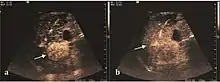

The suggestive appearance of early HCC on 2D ultrasound examination is that of hypoechoic nodule, with distinct pattern, developed on cirrhotic liver. Hypoechoic appearance is characteristic of moderate/poorly differentiated HCC, with low or absent fatty changes. Rarely, HCC may appear isoechoic, consist of a tumor type with a higher degree of differentiation and therefore with slower development. Another common aspect is "bright loop" or "nodule-in-nodule" appearance, hypoechoic nodules in a hyperechoic tumor.

Spectral Doppler characteristics of early HCC overlap those of the dysplastic nodule, as they are represented by the presence of portal venous signal type or arterial type with normal RI (well differentiated HCC) or increased RI (moderately or poorly differentiated HCC). The CFM exploration identifies a chaotic vessels pattern.

On CEUS examination, early HCC has an iso- or hypervascular appearance during the arterial phase followed by wash out during portal venous and late phase. There are studies showing that the wash out process is directly correlated with the size and features of neoplastic circulatory bed. Thus, highly differentiated HCC illustrates the phenomenon of late or even very late "wash out" while poorly differentiated HCC has an accelerated wash out at the end of arterial phase. It is therefore mandatory to analyze all these three phases of CEUS examination for a proper characterization of liver nodules. Tumor wash out at the end of the arterial phase allows the HCC diagnosis with a predictability of 89.5%. Some authors consider that early pronounced contrast enhancement of a nodule within 1–2 cm developed on a cirrhotic liver is sufficient for HCC diagnosis. These results prove that for a correct characterization of the lesions it is necessary to extend the examination time to 5 minutes or even longer.